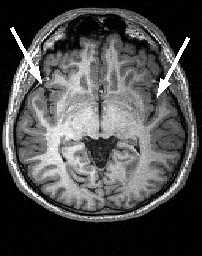

МРТ головного мозга. Аксиальной срез на уровне III желудочка. Сильвиева щель (стрелки).

МРТ головного мозга. Аксиальный срез. Боковые желудочки и подкорковые ядра (NC- хвостатое ядро, NL - чечевицеобразное ядро, Th - зрительный бугор). Инфратенториально расположены части ствола мозга (нижняя часть среднего мозга, мост и продолговатый мозг) и мозжечок.